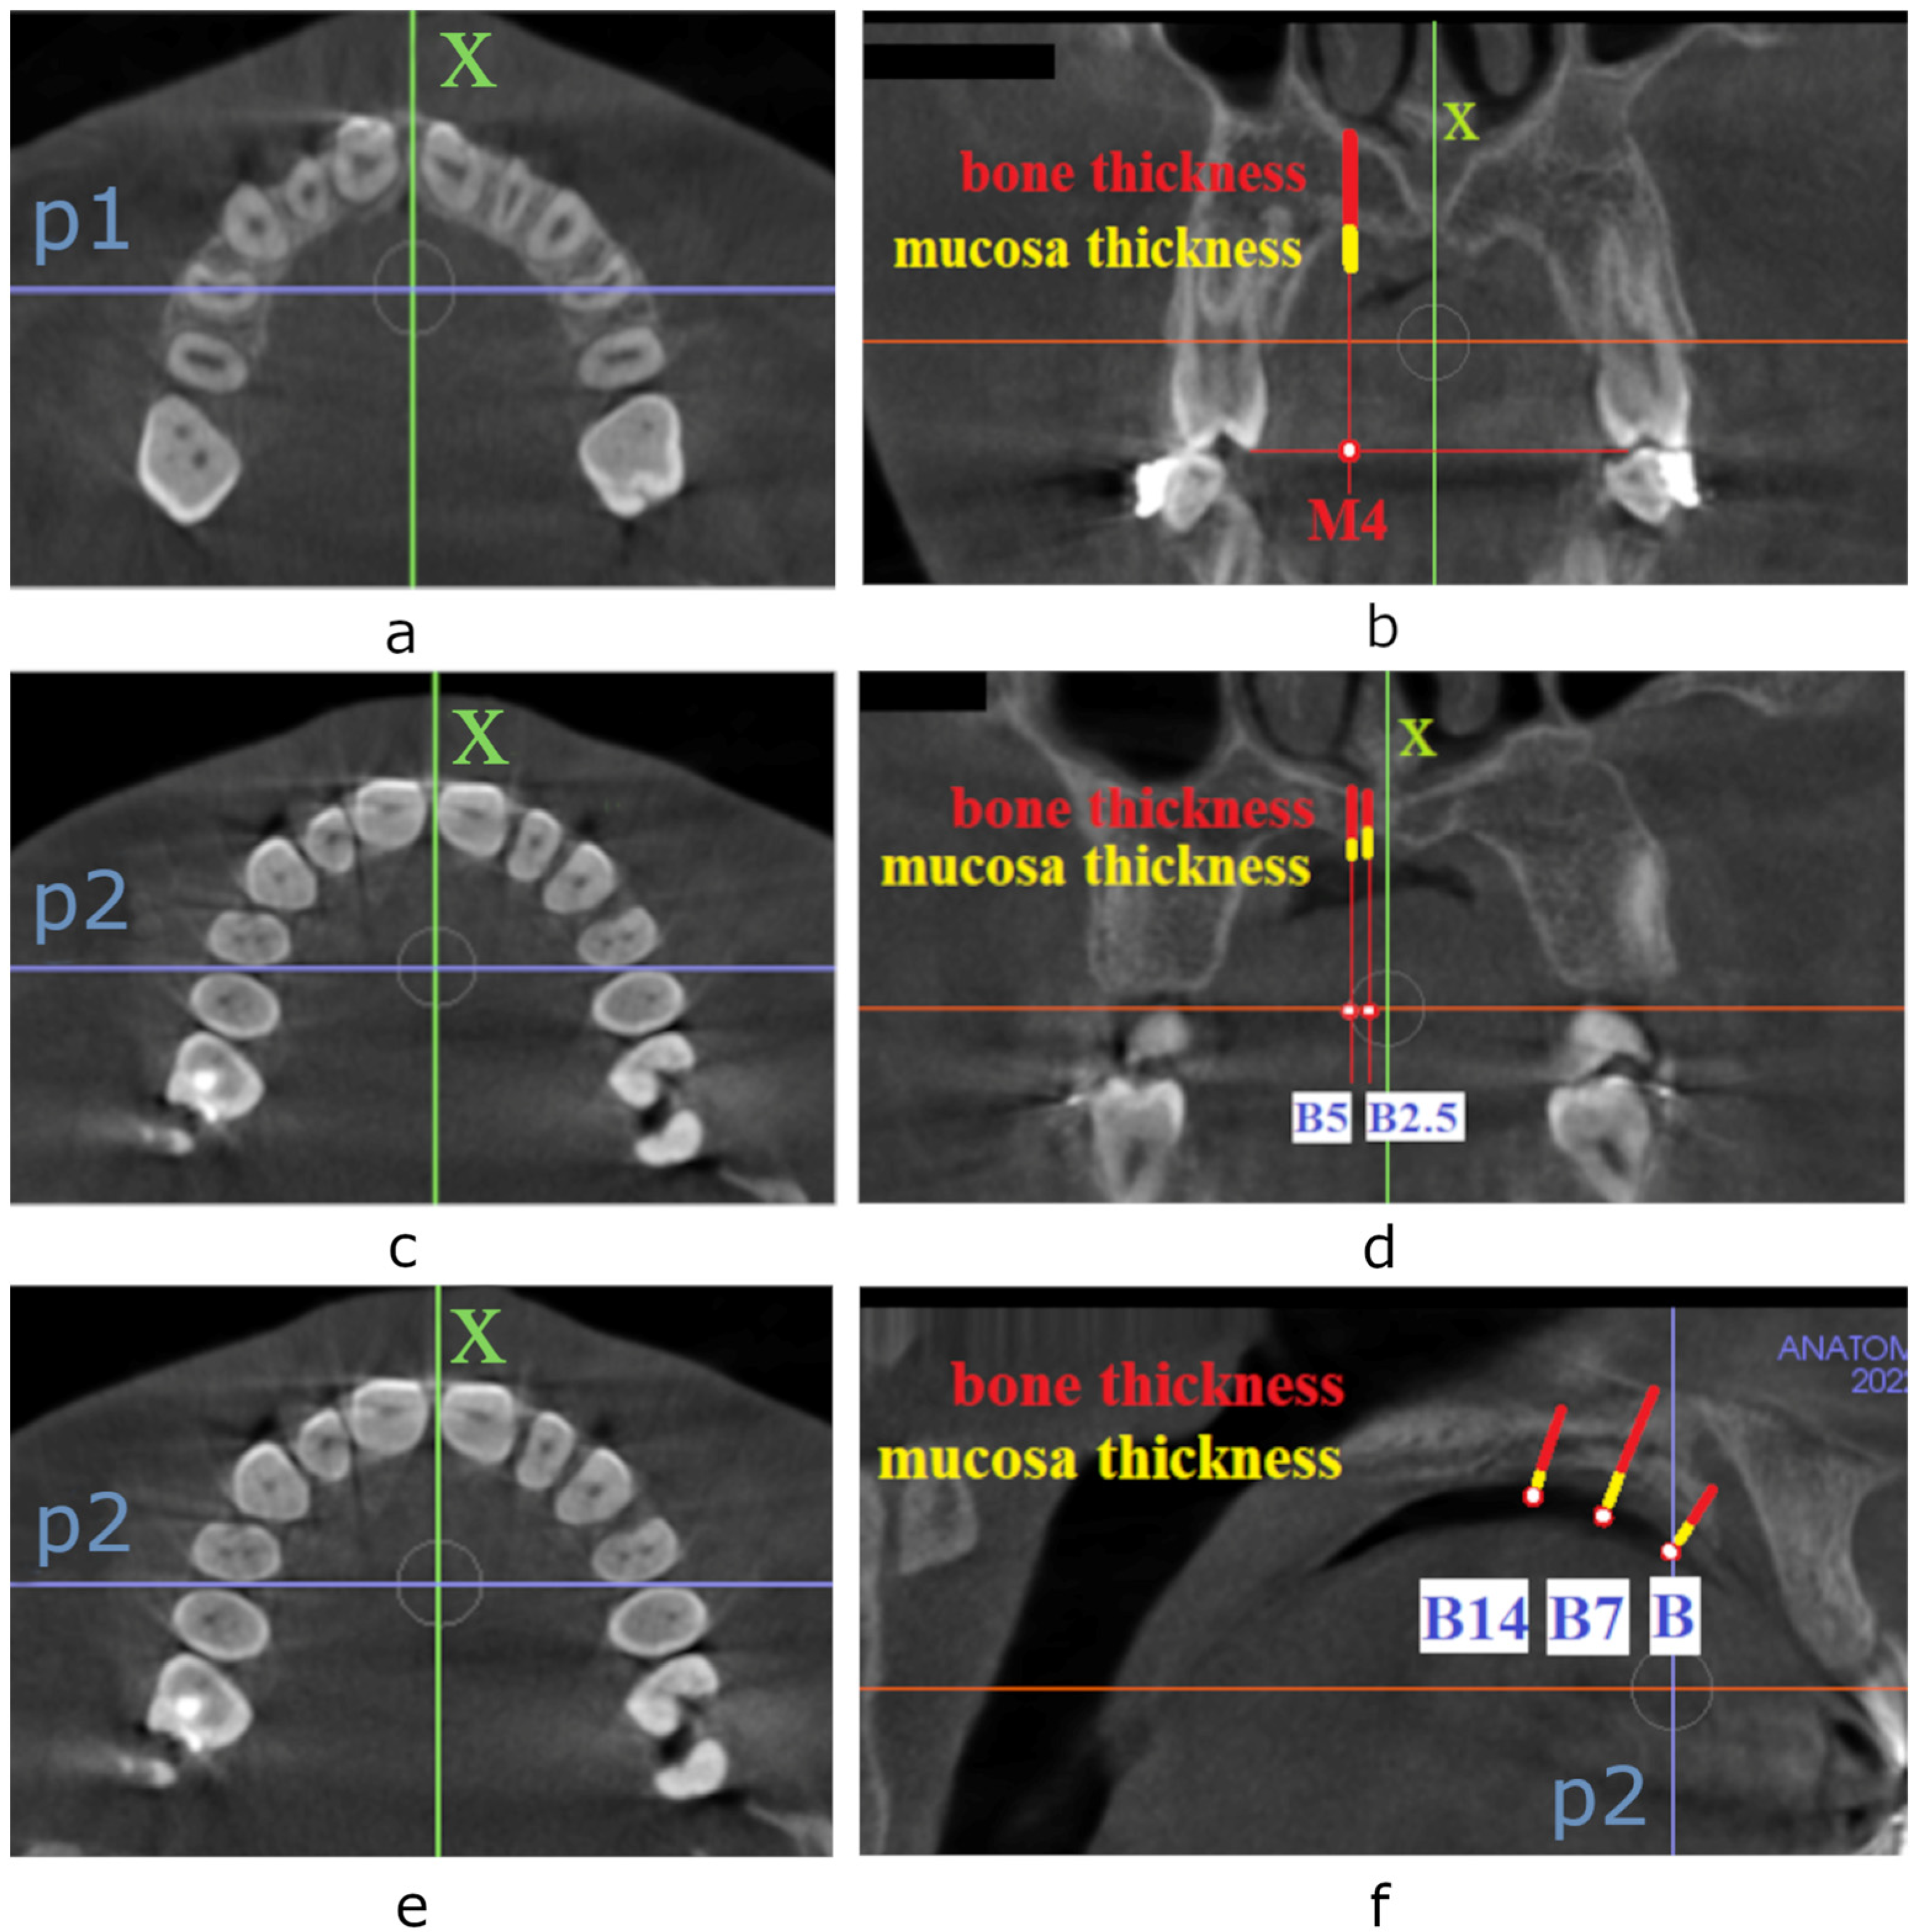

Figure 2.

CBCT screenshots of the horizontal and frontal plane with the reference lines and points constructed for tissue thickness measurement. Horizontal (a) and frontal (b) view of the maxilla with reference lines and points constructed for tissue thickness assessment in the case of insertion of TopJet miniscrew: x—the midline of the palate, p1—the line passing through the midpoints of crowns of first premolars, M4 point—half-distance from the palatal cusp of the first premolar to the midline of the palate; CBCT screenshots of the horizontal (c) and frontal (d) plane with the reference lines and points constructed for tissue thickness assessment for paramedian insertion of Benefit micro-implants: x—the midline of the palate, p2—the line passing between first and second premolar, B2.5 point—a point located 2.5 mm laterally to the x-axis, B5—a point located 5 mm laterally to the x-axis; CBCT screenshots of the horizontal (e) and sagittal (f) plane with the reference lines and points constructed for tissue thickness assessment for median insertion of Benefit micro-implants: x—the midline of the palate, p2—the line passing between first and second premolar, B point—a point located at the level of p2 line, B7 point—a point located 7 mm distally to p2 line, B14—a point located 14 mm distally to p2 line.

Measurements of bone and mucosa thickness were performed at six locations in the palate. In the first part of the study, tissue thickness for TopJet miniscrew was measured as presented in Figure 2a,b. The line passing through the middle of the oral opening of the nasopalatine canal and posterior nasal spine was designated as the midline of the palate (x-axis). The line passing through the midpoints of the crowns of the first premolars was determined as the p1-axis. The tissue thickness for TopJet microscrew was measured in coronal view at the M4 point (half-distance from the palatal cusp of the first premolar to the midline of the palate) [4] when the scan was oriented according to the p1-axis. The measurement was performed separately for the soft and hard tissues. Since previous studies presented no difference between the right and left side of the patient, only one side (right) was assessed for the purpose of this study [11,17].

In the second part of the study, tissue thickness for paramedian insertion of Benefit micro-implants was investigated as presented in Figure 2c,d. For the purpose of measurements, CBCT scans were positioned according to the p2 axis. Tissue thickness was assessed in the frontal plane at points B2.5 and B5 located 2.5 mm and 5 mm laterally to the x-axis and perpendicularly to the occlusal plane as recommended for paramedian insertion of Benefit miniscrews [12]. Soft and hard tissue thickness was measured.

In the last part of the study, tissue thickness for the median pattern of insertion of Benefit miniscrews was determined. According to the authors of the method, micro-implants should be placed along the x-axis 7–14 mm apart [12]. For the purpose of this measurement, the sagittal slice of CBCT was assessed when the scan was oriented according to p2 and x-axis. Mucosa thickness and palatal bone thickness were measured at the level of the p2 axis and 7 mm, and 14 mm distally, perpendicularly to the palate, as presented in Figure 2e,f.